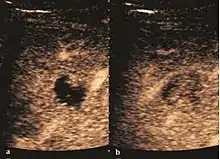

Dysplastic nodule (2D, CFM, CEUS). The nodule is well-defined with a size between 10– 20 mm, lacks vessels in CFM and CEUS exploration.

These lesions have various patterns (hypo or hyperechoic) with at least 1 cm diameter. They are hepatocytes with dysplastic changes, but without clear histological criteria for malignancy. They are divided into low-grade dysplastic nodules, where cellular atypia are mild and high-grade dysplastic nodules with moderate or severe cellular atypia, but without any established signs of malignancy. Occasionally, well-differentiated HCC foci can be identified in high-grade dysplastic nodules (appearance called "nodule in nodule") . Most authors accept the carcinogenesis process as a progressive transformation of DN from low-grade to high-grade and into HCC. The nodule's vasculature changes progressively, correlated with the degree of malignancy, and it is characterized by decrease until absence of portal venous input and by increase of arterial intratumoral input. Neoformation vessels occur with increasing degree of dysplasia. Arterial neovascularization is enhanced in a chaotic and explosive way, while normal, arterial and portal vasculature continues to decline. High-grade dysplastic nodules are hypovascularized both arterial and portal phases, while early HCC nodules may have similar arterial pattern with the surrounding parenchyma or exacerbated, and portal hypovascularization. In moderate or poorly differentiated HCC (classic HCC) tumor nutrition is performed only by neoformation vessels (abundant), the normal arterial and portal vasculature completely disappearing. This behavior of intratumoral vascularization is typical for HCC and is the key to imaging diagnosis.

B-mode ultrasonography is unable to distinguish between regenerative nodules and borderline lesions such as dysplastic nodules and even early HCC. Doppler examination also has a low sensitivity in differentiating dysplastic nodules from early HCC. Doppler signal may be absent in both regenerative and dysplastic nodules. Some authors indicate the presence of venous type Doppler flow which reflects the portal venous nutrition of the nodule as a characteristic feature of dysplastic nodules and early HCC (Minami & Kudo, 2010). Other authors noticed the presence of an arterial flow with small frequency variations and a normal resistivity index. On CEUS examination both RN and DN may have quite a variable enhancement pattern. Generally, both nodules enhances identically with the surrounding liver parenchyma after UCAs injection. Dysplastic nodules are hypovascular in the arterial phase. In case of highgrade dysplastic nodule sometimes a hypervascularization can be detected, but without associating "wash out" during portal and late CEUS phases. In these cases, biopsy may clarify the diagnosis.